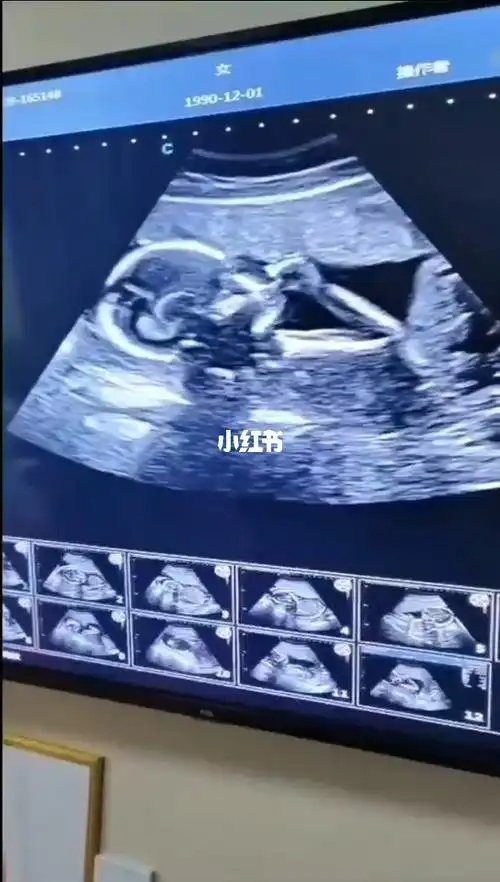

怀孕18周胎儿彩超图

做b超检查,才18周大的小胎儿在子宫里点了个赞

科普胎儿18周就能看出是否左撇子

胎儿18周的时候建议您到医院做一次全面的检查,通过b超您可以看到宝宝

嘿嘿,18周,这个图有人能看出来男女吗?